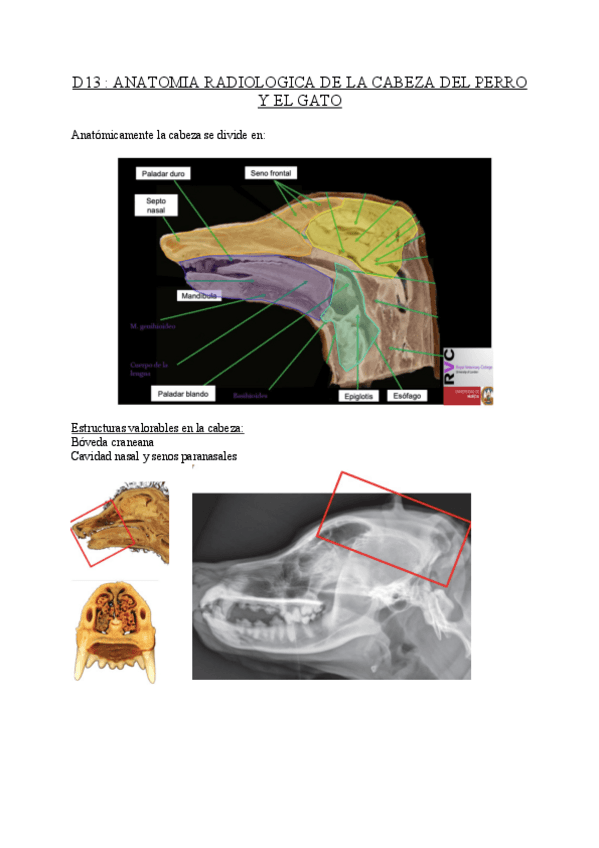

ANATOMIA-RADIOLOGICA-DE-LA-CABEZA-DEL-PERRO-Y-GATO.pdf